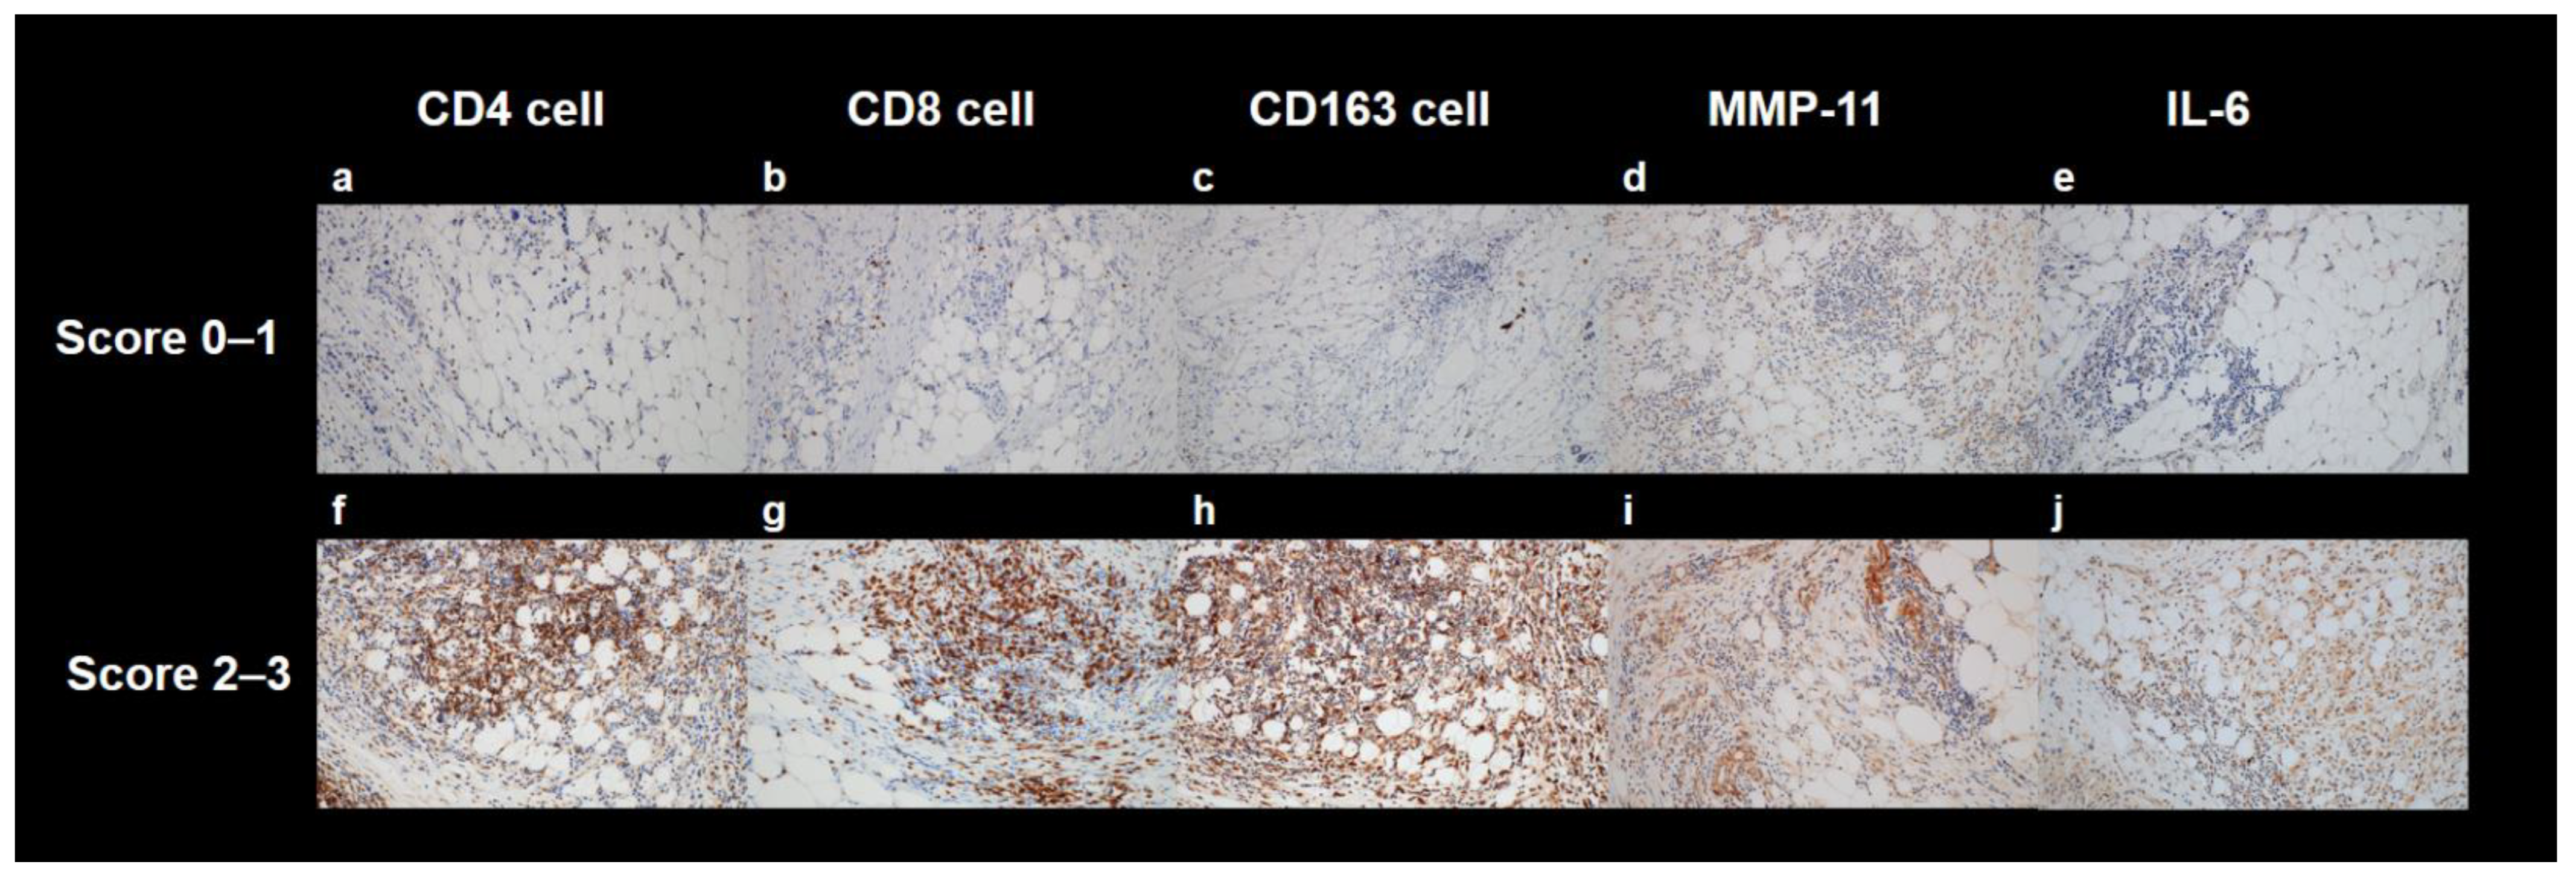

4.3. Histopathological Analysis